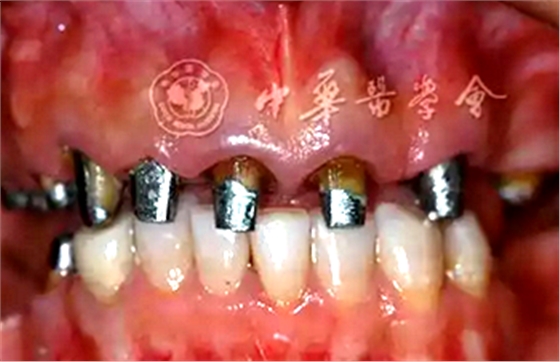

3.牙冠延長術(shù):

(2)手術(shù)導(dǎo)板指導(dǎo)下的牙冠延長術(shù):根據(jù)最終診斷蠟型,制作透明墊式手術(shù)導(dǎo)板(圖4B),指導(dǎo)上頜牙冠延長術(shù)(圖5),最終達到改善牙齦形、線、點的美學(xué)要求,獲得協(xié)調(diào)、對稱的美學(xué)效果。

圖5 有利于健康、功能及美學(xué)效果的牙冠延長術(shù)手術(shù)過程 A:戴入手術(shù)導(dǎo)板;B:在手術(shù)導(dǎo)板的指導(dǎo)下確定手術(shù)切口;C:翻瓣后可見唇側(cè)骨板肥厚、形態(tài)不佳,上前牙鄰面及唇側(cè)原有肩臺距離骨嵴頂≤ 2 mm,侵犯了生物學(xué)寬度;D:骨切除及骨成形后唇側(cè)骨板形態(tài),肩臺距牙槽嵴頂約4 mm;E:齦瓣復(fù)位縫合,原有肩臺均位于齦上